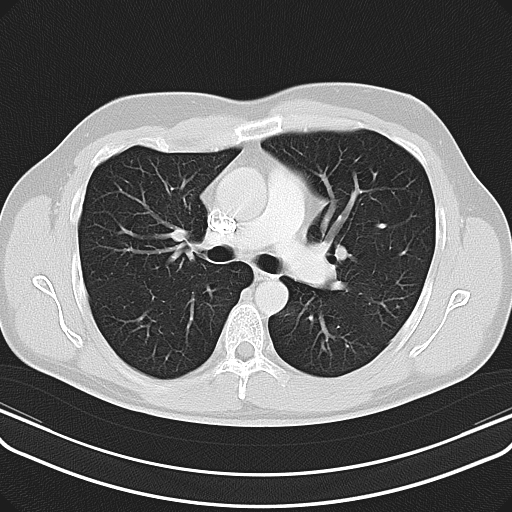

Die Diagnose von Tumoren, Entzündungen, Gefäßerkrankungen oder Verletzungen ist in der modernen Medizin ohne den Einsatz der Computertomographie inzwischen undenkbar. Die besondere Stärke der CT liegt in der hohen räumlichen Auflösung. Bei der Abklärung knöcherner Strukturen z.B. des Innenohrs oder der Nasennebenhöhlen ist diese Methode nicht mehr wegzudenken. Auch für die Feinbeurteilung der Lunge gibt es zur CT keine Alternative.

- Zum Ausschluss von Tumoren, Metastasen, Embolien oder Entzündungen der Lunge

– der Lungenfeinstruktur